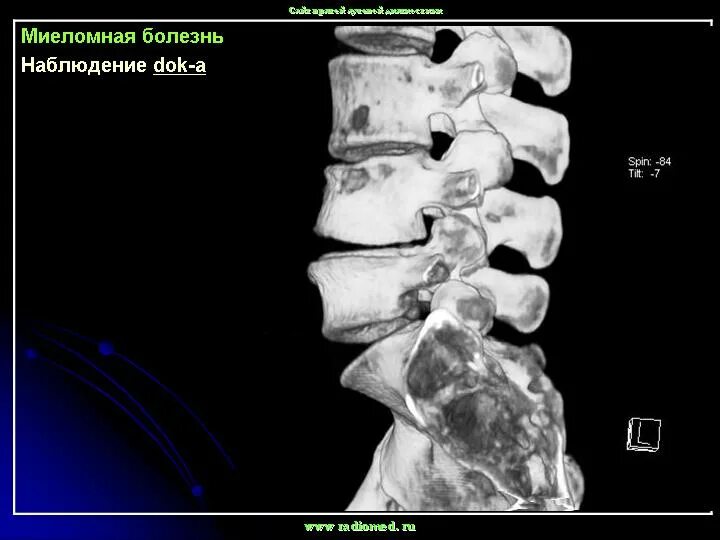

Сколько живут с метастазами в позвоночнике